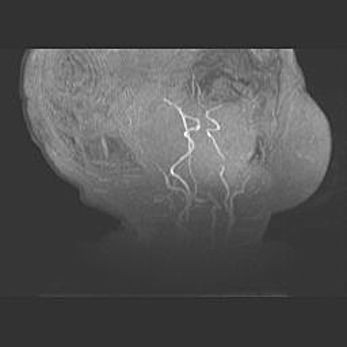

Подострая гематома правой гемисферы мозжечка.

Наружная гидроцефалия.

Возраст: 15 дней

Вес: 3100 г

Пол: женский

Окружность головы: 37 см

Срок гестации: 35-36 недель

При открытой наружной форме гидроцефалии у новорожденных расширяются и переполняются субарахноидные пространства.

Кровоизлияния в мозжечок имеют две клинико-анатомические формы: полушарные гематомы и кровоизлияния в червь.

К появлению этой патологии может привести: повреждения головного мозга, возникающие в результате асфиксии и гипоксии плода при беременности, или травмы во время родов. Редко гематома мозжечка может быть результатом первичной коагулопатии и сосудистой мальформации, диссеминированном внутрисосудистом свертывании, изоиммунной тромбоцитопении.